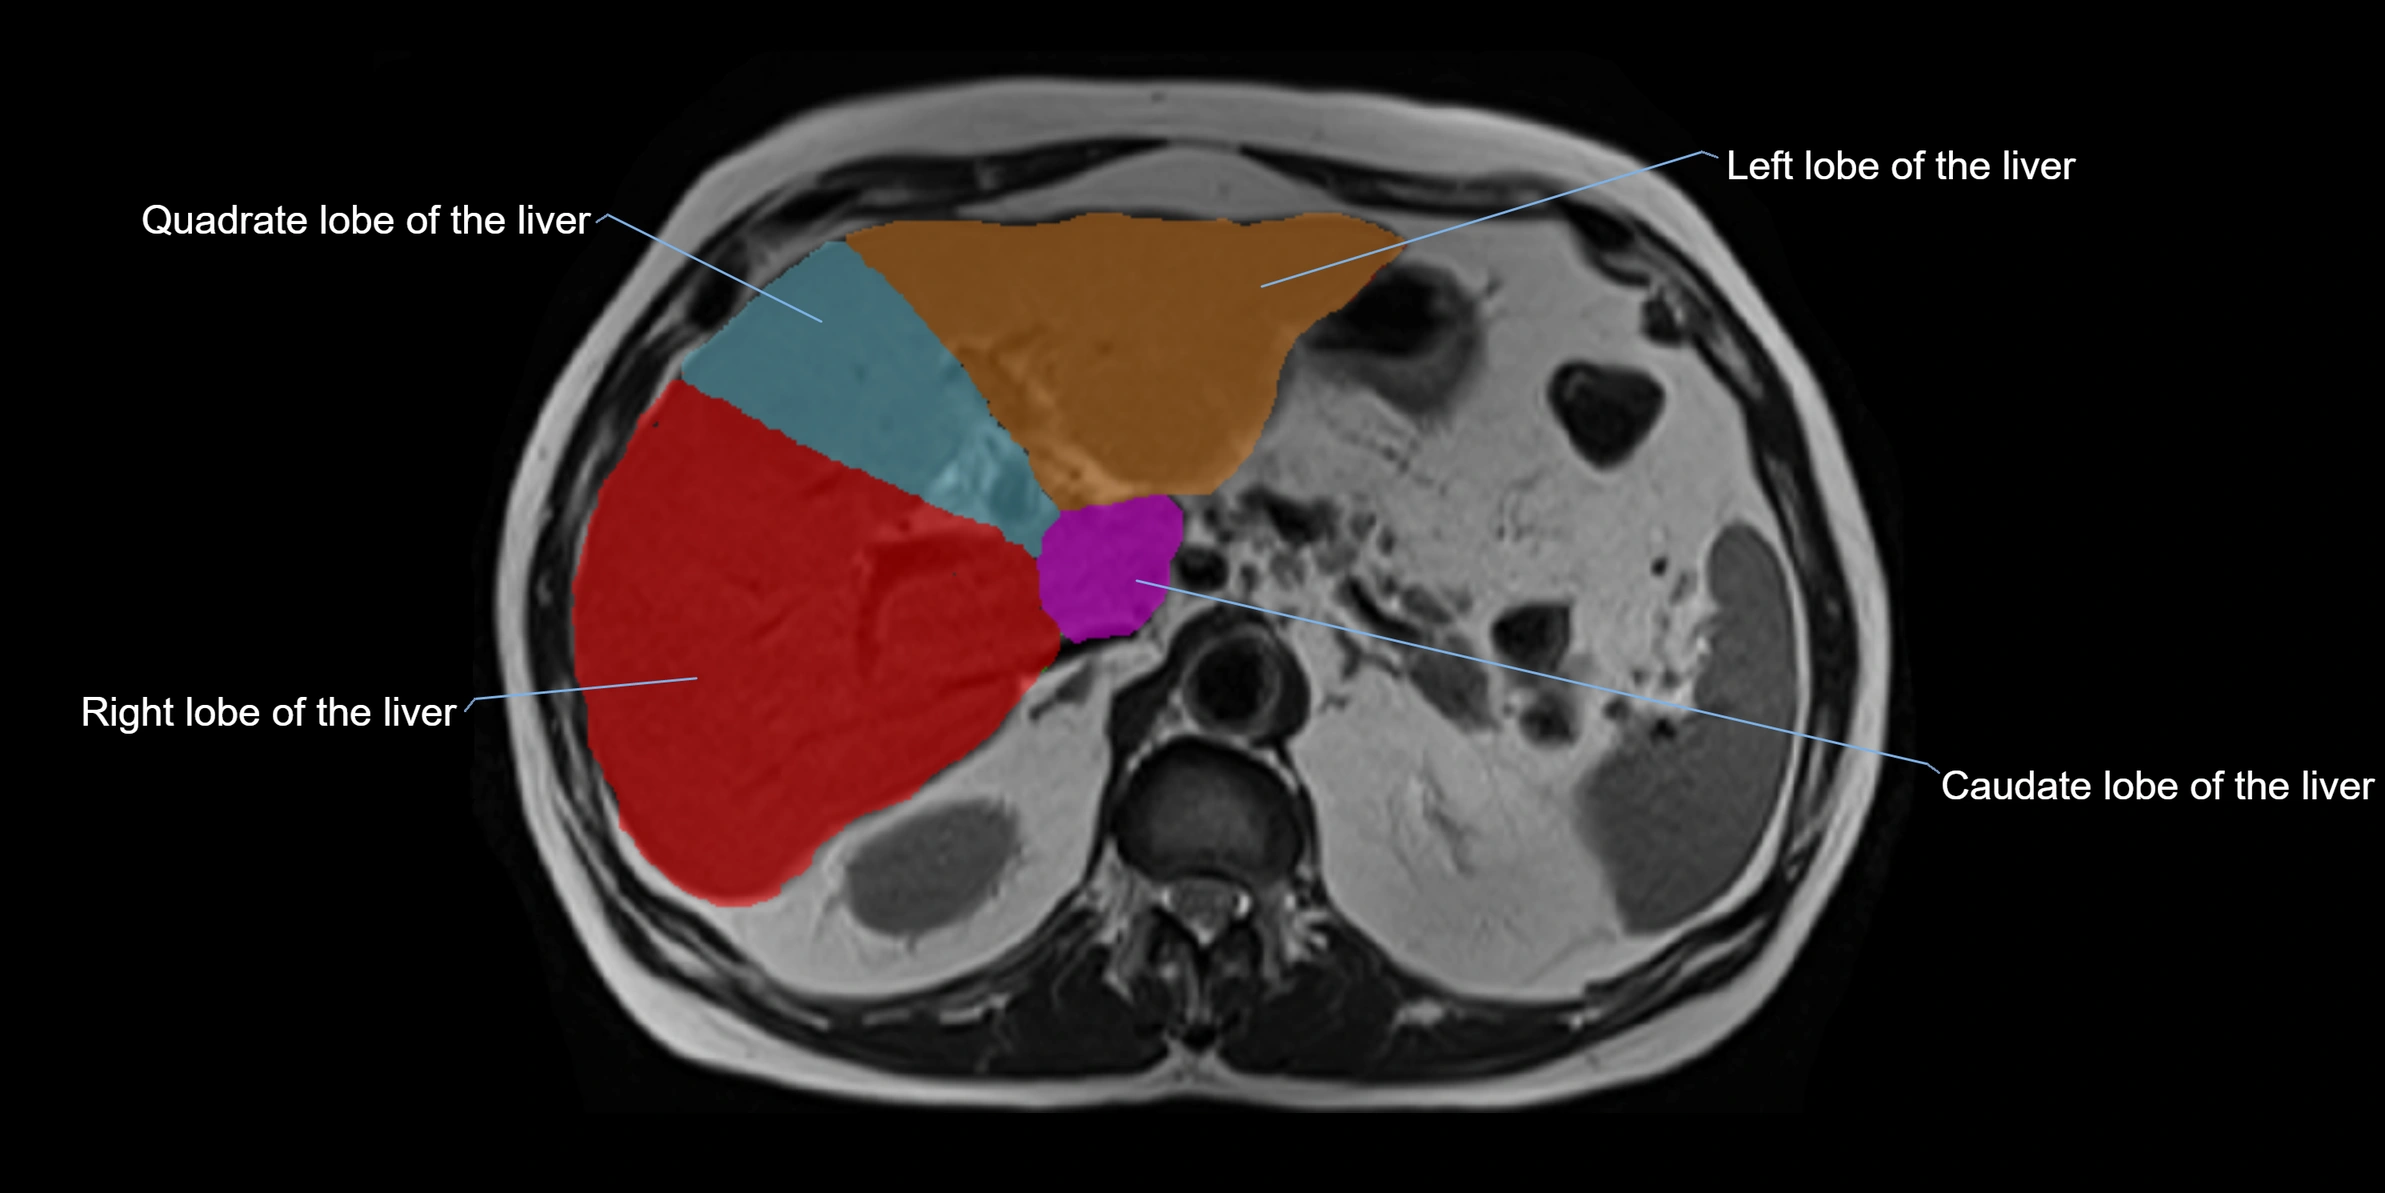

The caudate lobe of the liver is a distinct anatomical subdivision of the liver, designated as segment I in Couinaud’s classification. It lies on the posterior surface of the liver, between the fissure for the ligamentum venosum (left boundary) and the groove for the inferior vena cava (IVC) (right boundary). Superiorly, it is related to the posterior liver surface, and inferiorly it is separated from the left lobe by the porta hepatis.

The caudate lobe is unique because it receives dual portal venous and arterial inflow from both the right and left portal veins and hepatic arteries. It also has independent venous drainage directly into the IVC via multiple small hepatic veins, unlike other lobes that drain through the three main hepatic veins.

This anatomical autonomy makes the caudate lobe especially significant in liver surgery, transplantation, and hepatic venous outflow obstruction syndromes (e.g., Budd–Chiari syndrome). Enlargement of the caudate lobe is a characteristic imaging feature in chronic liver disease and cirrhosis.